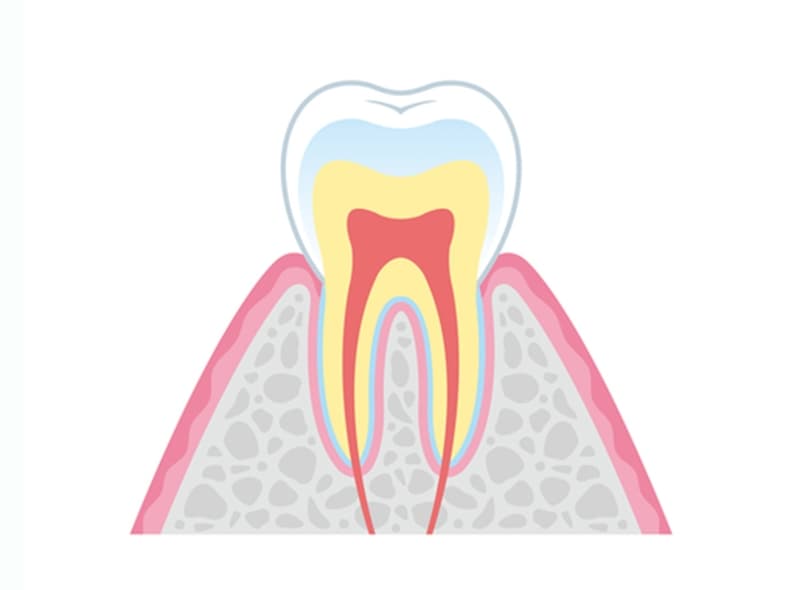

- C0

初期のむし歯

初期のむし歯は、白濁した斑点(白斑)として観察されることがあります。この段階では、歯質の破壊はまだ少ないので、非侵襲的なアプローチ(フッ素塗布やクリーニングなど)により、進行を抑制できる可能性があります。定期的なモニタリングにより、リスクを評価しながら管理していくことが重要です。